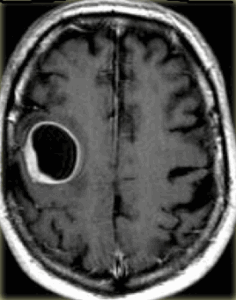

К посттравматическим изменениям можно отнести гипертрофическую дегенерацию оливкового ядра, которая наблюдается крайне редко чрез 3-6 месяцев после травмы. При МРТ головного мозга выявляется повышенный сигнал на Т2-взвешенных МРТ с одной или двух сторон.

МРТ головного мозга. Т2-взвешенная аксиальная МРТ. Гипертрофическая дегенерация левого оливкового ядра.